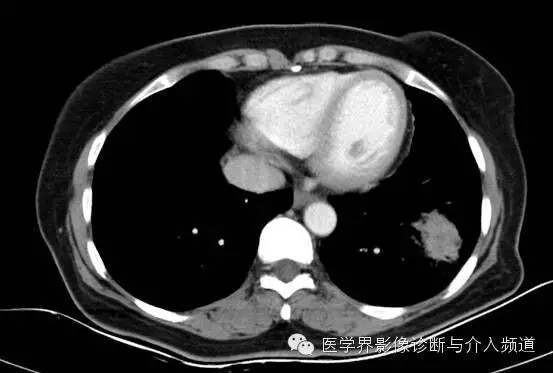

左下肺硬化性血管瘤1例CT影像表现

左肺下叶可见软组织密度肿块影,形态不规则,边界不光整,与胸膜粘连不清,周围肺组织呈磨玻璃密度改变,病变内部不均匀强化,低密度区不强化。

硬化性血管瘤

病变部位:右肺下叶居多,既可位于中央区,也可位于周围带,靠近胸膜,极少数位于叶间裂。

综上,若女性,发现肺内单发圆形或类圆形肿块,边界光整,内部看见囊变,若还有空气新月征、晕征、周围肺组织肺气肿、钙化,增强扫描明显均匀强化,应考虑硬化性血管瘤的可能。